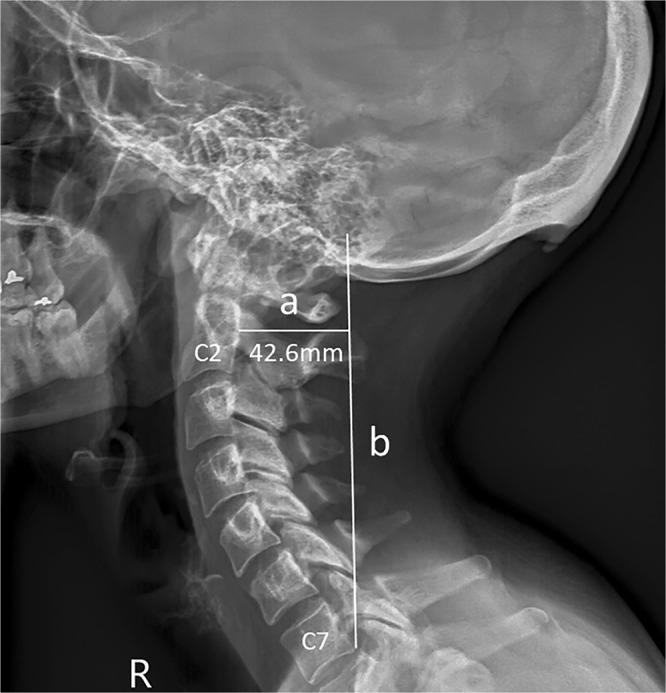

Prominent exostosis projecting from the occipital squama more substantial and prevalent in young adult than older age groups.

Recently we reported the development of prominent exostosis young adults' skulls (41%; 10-31 mm) emanating from the external occipital protuberance (EOP). These findings contrast existing reports that large enthesophytes are not seen in young adults. Here we show that a combination sex, the degree of forward head protraction (FHP) and age predicted the presence of enlarged EOP (EEOP) (n = 1200, age 18-86). While being a male and increased FHP had a positive effect on prominent exostosis, paradoxically, increase in age was linked to a decrease in enthesophyte size. Our latter findings provide a conundrum, as the frequency and severity of degenerative skeletal features in humans are associated typically with aging. Our findings and the literature provide evidence that mechanical load plays a vital role in the development and maintenance of the enthesis (insertion) and draws a direct link between aberrant loading of the enthesis and related pathologies. We hypothesize EEOP may be linked to sustained aberrant postures associated with the emergence and extensive use of hand-held contemporary technologies, such as smartphones and tablets. Our findings raise a concern about the future musculoskeletal health of the young adult population and reinforce the need for prevention intervention through posture improvement education.

最近,我们报道了年轻人颅骨(41%;10-31mm)外枕外隆凸(EOP)出现明显外生骨赘的情况。这些发现与现有的报告相矛盾,即年轻人的大附着点骨赘没有被发现。在这里,我们展示了性别、头部前伸程度(FHP)和年龄的组合可以预测 EOP 增大(EEOP)的存在(n=1200,年龄 18-86 岁)。虽然男性和 FHP 增加对明显外生骨赘有积极影响,但矛盾的是,年龄的增加与附着点骨赘的大小减少有关。我们的后一个发现提出了一个难题,因为在人类中,骨骼退行性特征的频率和严重程度通常与衰老有关。我们的发现和文献提供了证据,证明机械负荷在附着点(插入)的发育和维持中起着至关重要的作用,并在附着点的异常负荷和相关病变之间建立了直接联系。我们假设 EEOP 可能与与手持现代技术(如智能手机和平板电脑)的出现和广泛使用相关的持续异常姿势有关。我们的发现引起了对年轻成年人未来肌肉骨骼健康的关注,并强调需要通过改善姿势教育进行预防干预。